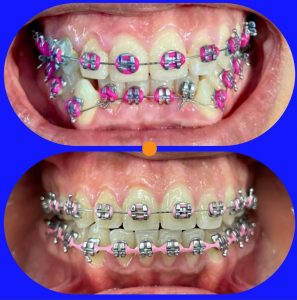

Tratamientos Ortodoncia Blanqueamiento dental Zoom Contacto 72 2795 9597 Marcar Ahora Envia whatsapp Visita nuestro facebook